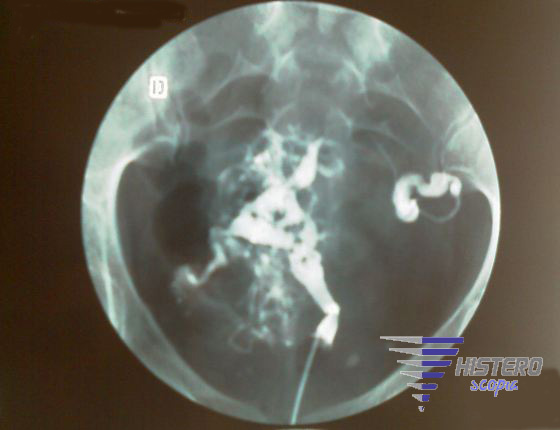

asherman1  adherencia lateral asherman3

asherman4 asherman5 asherman6

asherman9 asherman7 asherman10

asherman hsg 2   1329_3 copia  1164_3 copia